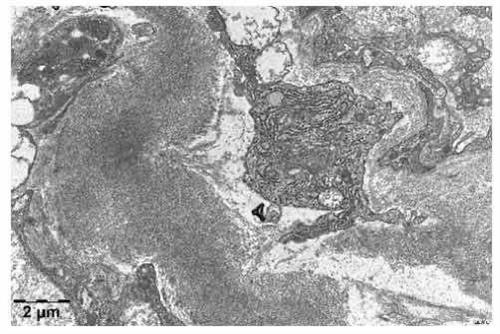

巴基斯坦前總統穆沙拉夫于今年的2月初,由于罕見病淀粉樣變性,與世長辭,享年79歲。穆沙拉夫的故事使得他所患的淀粉樣變性,這種罕見病再次進入了大眾的視野。潮新聞記者在今年國際罕見病來臨之前,采訪了淀粉樣變性患者的家屬,以及相關的權威專家,為大家帶來詳細的關于淀粉樣變性這種罕見病的解析。

1. 淀粉樣變性這一罕見病,實際上跟淀粉是沒有任何關系的,異常蛋白質有著非常密切的關系。

2. 人類患上這種疾病,就會導致異常蛋白質在血液中出現,而這一種異常的蛋白質是無法被消化掉的,也不能夠被在人體中被排出來,會隨著人體的血液在四處漂流,逐漸在皮膚,心臟以及腎臟等處積累。人體不斷的會產生這種蛋白質,也就會有更多的這種物質積累在一起,就好像淀粉一樣。